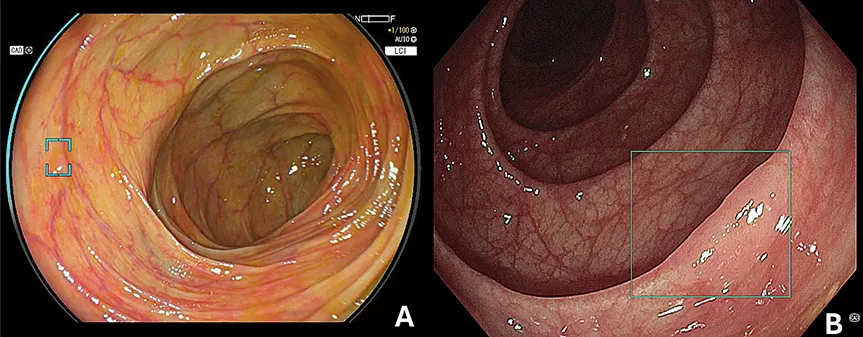

Figure 4 : Exemple de score Mayo automatisée per endoscopie avec le système « Smart IBD Olysense, Olympus »

Applications spécifiques à l’œsophage Carcinome épidermoïde

• La SFED pour les illustrations sur le score de Mayo